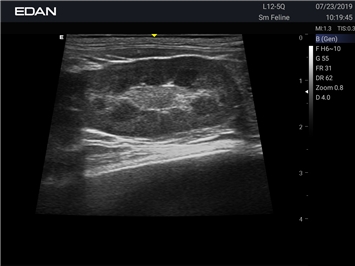

EDAN Acclarix AX2 VET

Ветеринарный ультразвук одним нажатием. Система Acclarix AX2 VET разработана с целью обеспечить бескомпромиссную производительность по доступной цене. Наличие уникальных двойных аккумуляторов в легком корпусе массой 4,5 кг из магниевого сплава позволяет системе Acclarix AX2 VET удовлетворять все потребности ветеринарных исследований, сохранив низкую стоимость.

EDAN Acclarix AX2 VET представляет собой специализированную ветеринарную ультразвуковую систему, сочетающую высокую производительность с доступной ценой. Благодаря продуманной конструкции и передовым технологиям, система обеспечивает качественную диагностику животных различных видов.